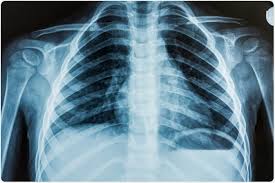

Acute respiratory distress syndrome, or ards, is an inflammatory lung injury that happens when fluids build up in small air sacs (called alveoli) in the lungs. Causes may include sepsis, pancreatitis, trauma, pneumonia, and aspiration. This lecture will cover ards pathophysiolo. It occurs when fluid fills up the air sacs in your lungs. Acute respiratory distress syndrome (ards) occurs when fluid builds up in the tiny, elastic air sacs (alveoli) in your lungs. Acute respiratory distress syndrome (ards) is a severe lung condition. Care guide for ards (acute respiratory distress syndrome) (discharge care). This month marks the 50th anniversary of the first description of the condition now termed the acute respiratory distress syndrome, or ards. The outcomes tend to be better in younger patients, trauma patients and when ards is caused by blood transfusions. Acute respiratory distress syndrome affects 200,00 people in the us each year. People who develop ards are usually ill due to another disease or a major injury. The american lung association (ala) says ards is a rapidly progressive disease that can occur in critically ill patients—most notably now, in those diagnosed with severe illness resulting from. On a microscopic level, the disorder is associated with capillary endothelial injury and diffuse alveolar damage.

The outcomes tend to be better in younger patients, trauma patients and when ards is caused by blood transfusions. This lecture will cover ards pathophysiolo. Breathing becomes difficult and oxygen cannot get into the body. Too much fluid in your lungs can lower the amount of oxygen or. Symptoms include shortness of breath (dyspnea), rapid breathing (tachypnea), and bluish skin coloration (cyanosis).

The acute respiratory distress syndrome (ards) is a common cause of respiratory failure in critically ill patients and is defined by the acute onset of noncardiogenic pulmonary oedema, hypoxaemia and the need for mechanical ventilation. The fluid prevents your lungs from filling with oxygen. In ards, fluid builds up inside the tiny air sacs of the lungs, and surfactant breaks down. People who develop ards are usually ill due to another disease or a major injury. Ards is a medical emergency. Acute respiratory distress syndrome, or ards, is an inflammatory lung injury that happens when fluids build up in small air sacs (called alveoli) in the lungs. Possible causes, signs and symptoms, standard treatment options and means of care and support. Acute respiratory distress syndrome (ards) is a condition that causes fluid to build up in your lungs so oxygen can't get to your organs.

This month marks the 50th anniversary of the first description of the condition now termed the acute respiratory distress syndrome, or ards. Breathing becomes difficult and oxygen cannot get into the body. In ards, fluid builds up inside the tiny air sacs of the lungs, and surfactant breaks down. Acute respiratory distress syndrome (ards) is a condition that causes fluid to build up in your lungs so oxygen can't get to your organs. Acute respiratory distress syndrome (ards) is a form of acute lung injury and occurs as a result of a severe pulmonary injury that causes alveolar damage heterogeneously throughout the lung. The condition leads to a buildup of fluid in the air sacs which prevents enough oxygen from passing into the bloodstream. The authors of this review discuss our current understan. Ards is a medical emergency. Acute respiratory distress syndrome (ards) is a serious lung condition that causes low blood oxygen. Too much fluid in your lungs can lower the amount of oxygen or. For those who survive, a decreased quality of life is common. Ards progresses through several phases after a direct pulmonary or indirect extrapulmonary insult. The diagnosis of ards is based on fulfilling three criteria: